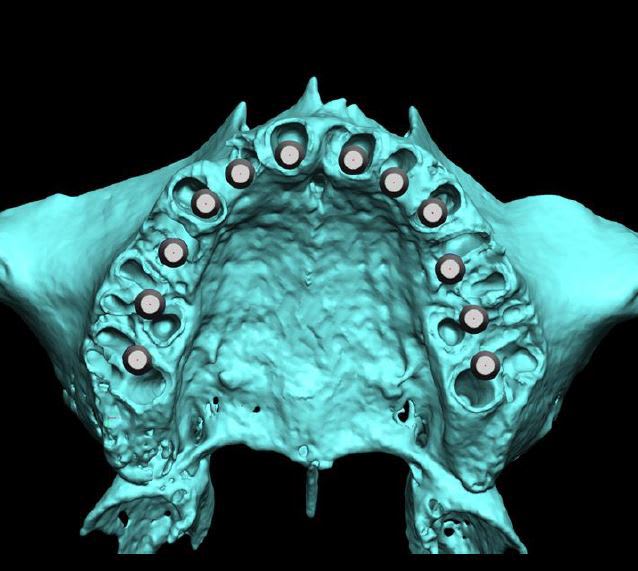

tous les implants sont en diamètre 3.7

certains (j'en fais partie) aiment bien plus large au niveau des secteurs molaire....mais vu que l'on a posé dans les septums, une augmentation de diamètre conduisait obligatoirement à une diminution de la surface de contact os/implant...d'où ce choix...

pano initiale et planche 3D montrant qu'en fait les molaires ne tenaient quasi plus que par les racines palatines...

pour la très grande précision d'emblée, Posit a répondu, nous sommes quelques praticiens à poser ainsi...

seules vraies difficultés: avoir parfaitement compris le système du guide Positdental et connaître/maîtriser parfaitement son système implantaire...